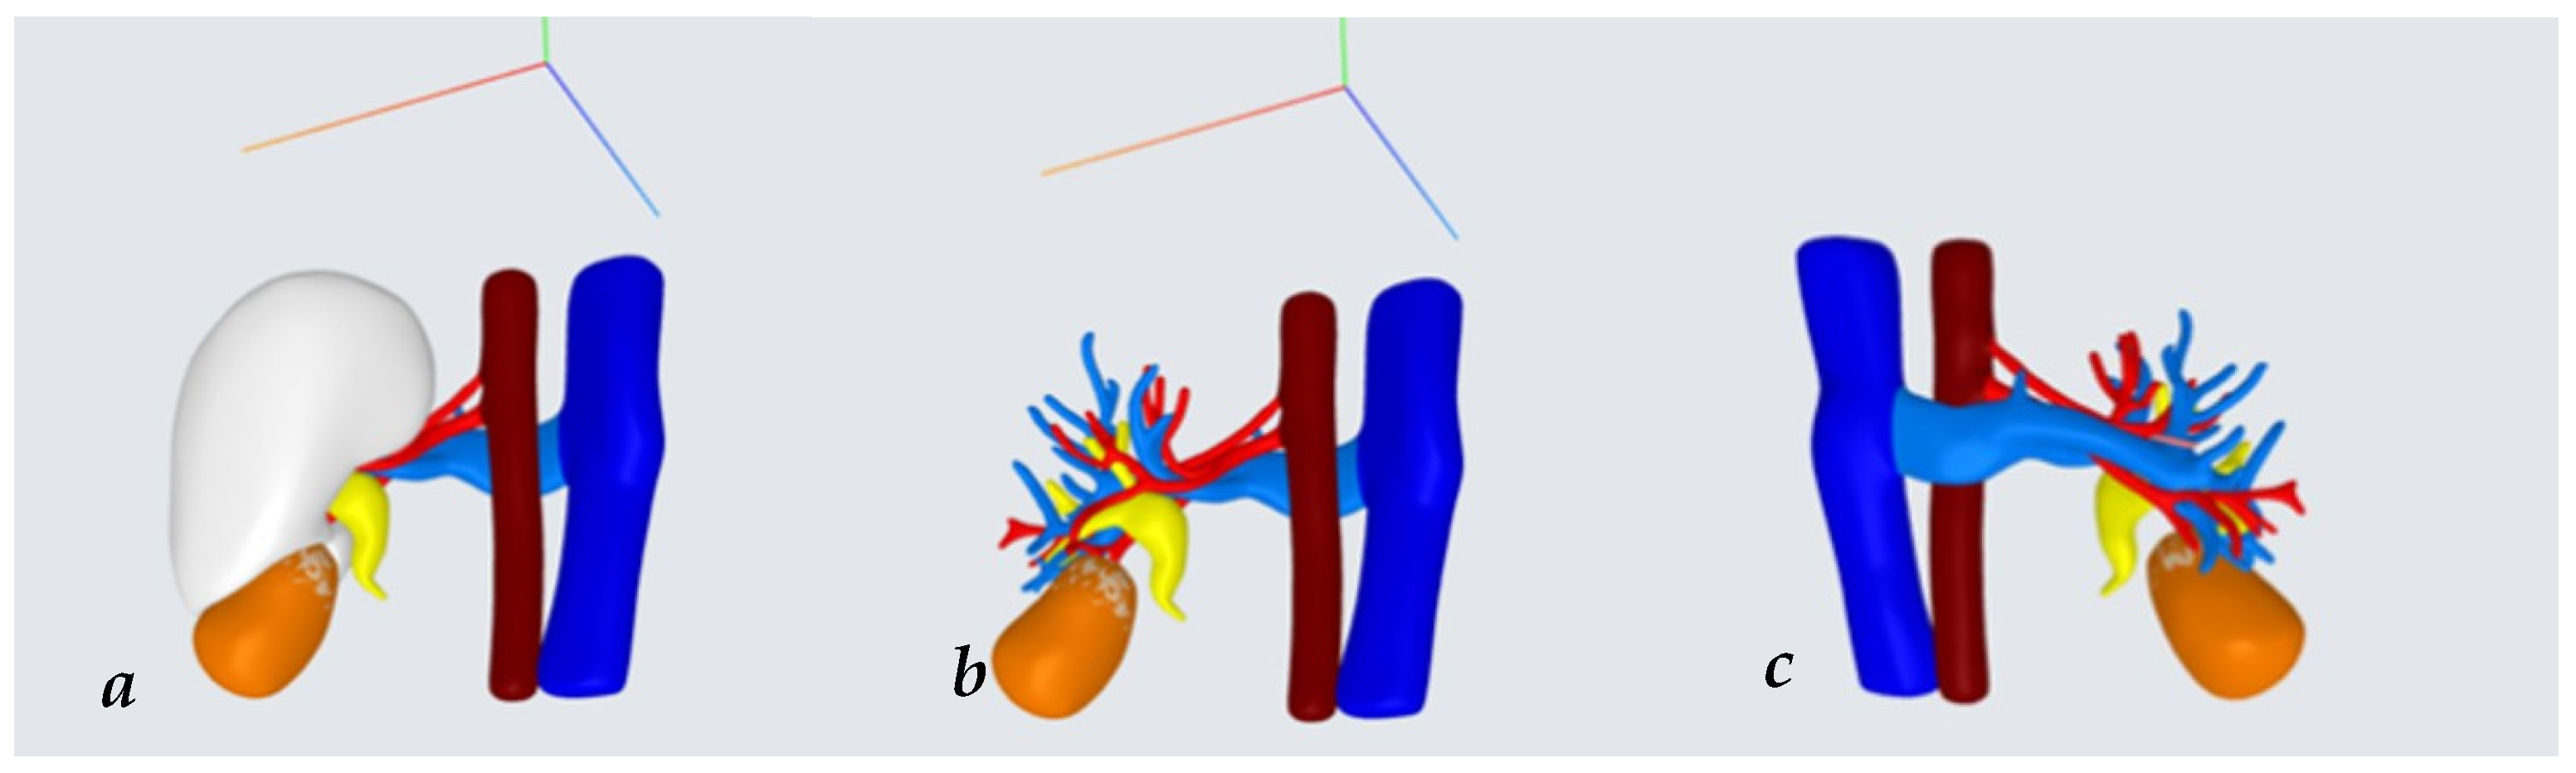

After a case discussion at multidisciplinary oncologic meetings, upfront surgery was planned. A three-dimensional (3D) reconstruction of the mass was performed (Medics Srl©, Moncalieri, Turin, Italy) (Figure 3a–c). At the age of 15, the boy underwent robot-assisted tumor enucleation. According to the UMBRELLA-SIOP Protocol, hilar and para-aortic lymphadenectomy were also performed [8,9]. During NSS, thanks to the 3D virtual reconstruction, only the inferior branch of the renal artery supplying the tumor was clamped using a single laparoscopic bulldog clamp (Aesculap, Tuttlingen, Germany). Indocyanine green injection (ICG) confirmed proper tumor ischemia, with well-preserved perfusion of the upper two-thirds of the kidney (Figure 4a–c).

Figure 3. (ac) Virtual 3D reconstruction. (a) Posterior view; (b) posterior view where kidney is excluded; (c) anterior view of tumor. Legend: tumor = orange, kidney = white, arterial vessels and aorta = red, venal vessels and vein cava = blue.